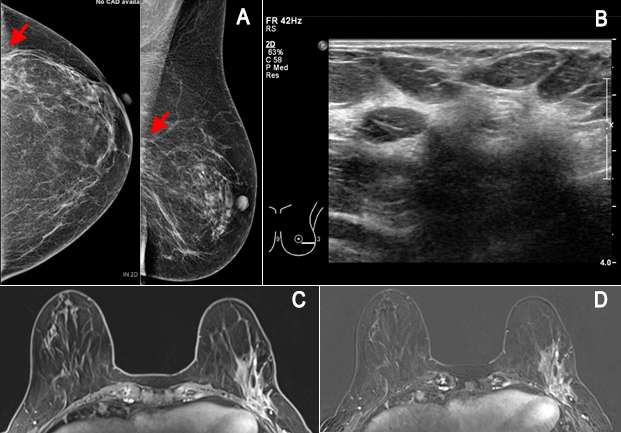

MRI is often used preoperatively to image the extent of breast cancer, including assessment of chest wall invasion, satellite lesions or multifocal/multicentric disease (additional cancer) to guide management and surgical approach. However, it is a somewhat controversial indication without additional high risk factors because the detection of more disease at MRI has not translated to improved outcomes or survival3. For instance, breast MRI is indicated in patients with biopsy-proven invasive lobular carcinoma due to its propensity to be multifocal/multicentric and affect the ipsilateral breast, which is seen in 20-29% of cases4. Studies have consistently shown a decreased repeat surgery rate when preoperative MRI was utilized3. Although somewhat controversial, breast MRI has been used in evaluating the extent of disease in patients with dense breasts where mammographic assessment was suboptimal. It can also be a useful tool to detect the primary breast cancer in patients with biopsy-proven axillary lymph node metastasis and normal mammogram and ultrasound5. Lastly, breast MRI has been shown to be successful in detection of residual disease after lumpectomy with positive margins, which is seen as asymmetric and nodular enhancement that is noncontiguous with the biopsy site5.

There are few circumstances where MRI is used as an adjunct to diagnose equivocal (uncertain) findings on mammography, sonography or physical examination. The first indication is a patient with persistent bloody or cytologically abnormal nipple discharge. MRI may also be useful for a suspicious finding seen only on one mammographic view that is not amenable to conventional biopsy. Breast MRI is also indicated in the evaluation of clinically suspected silicone implant abnormality or rupture. Due to its high spatial resolution and the contrast between implants and soft tissues, it has the highest sensitivity and specificity for implant rupture among imaging modalities and can be used to assess associated complications involving the surrounding breast tissue, chest wall and axilla7. Lastly, it can be used to evaluate patients with unclear but persistent physical examination findings that are mammographically and sonographically occult5.